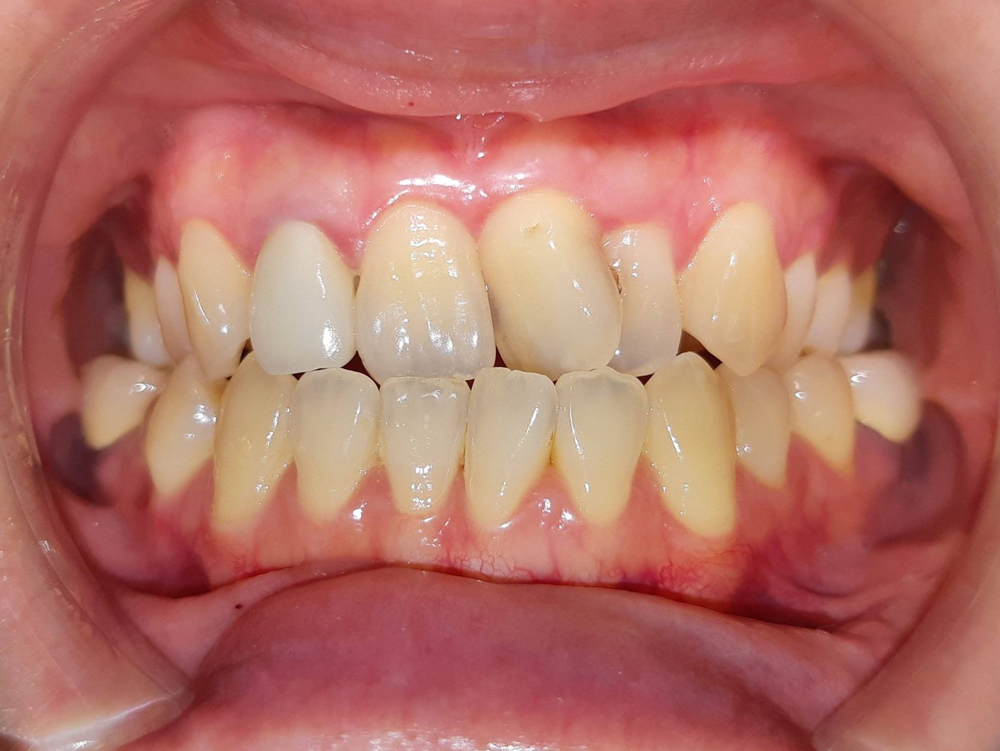

案例:不開刀齒性戽斗前後比較